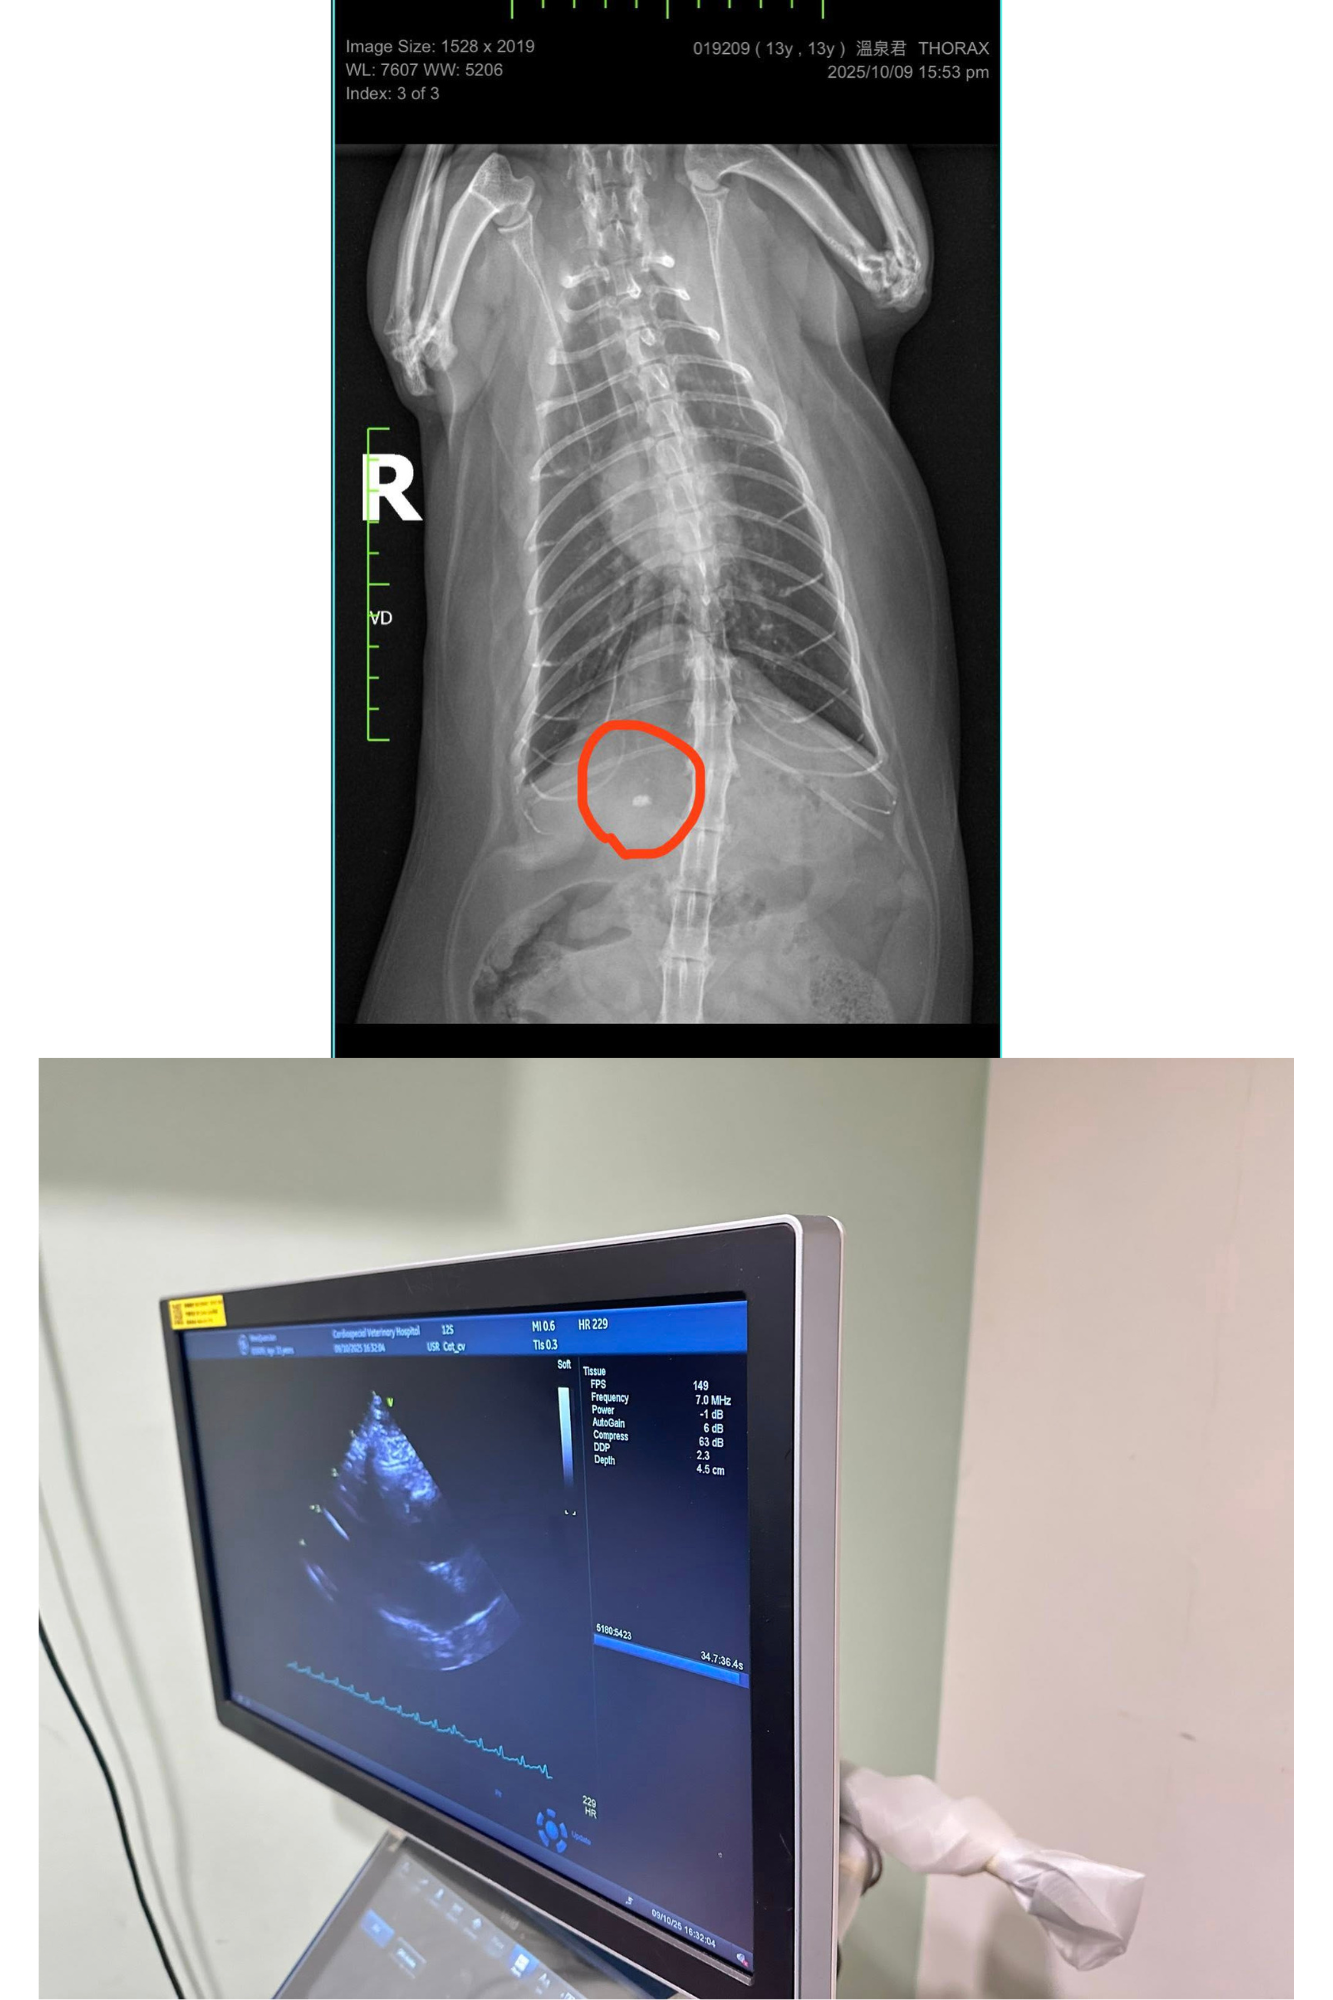

2025年10月9日誌專心醫院進行心臟檢查,今日主要做心臟的X光、超音波檢查、心電圖檢測。血壓正常無明顯心雜音。胸腔X光發現心臟輪廓大小正常,未見肺積水或胸膜積液證據。

右前腹腔影像有一礦物化物質,疑似膽結石,不確定是皮下或腹腔內,但需詳細確認的話,需用超音波檢測。總體來說,溫泉君心臟維持的不錯,無惡化。平時請密切監控心跳與呼吸,請避免過度興奮緊張與任何明顯加快心跳的理由。

2025/10/9 溫泉君 專心回診 陳炫甄醫師

體重:5.36kg(9/19在沐恩是5.25kg)

今日主要做心臟的X光、超音波檢查、心電圖檢測。

血壓正常120-130,無明顯心雜音。

胸腔X光發現心臟輪廓大小正常,未見肺積水或胸膜積液證據。

右前腹腔影像有一礦物化物質,疑似膽結石,不確定是皮下或腹腔內。

但需詳細確認的話,需用超音波檢測。

心臟超音波發現左心房大小與三年前相比,一樣是肥厚心肌病,但無明顯變大。屬於B1期。

心電圖的部分,沒有傳導的異常,心跳檢測時有因緊張過快,但並沒有早跳停拍的狀況。

醫師另外建議溫泉君可追蹤甲狀腺濃度的變化。

總體來說,溫泉君心臟維持的不錯,無惡化。

平時請密切監控心跳與呼吸,請避免過度興奮緊張與任何明顯加快心跳的理由。